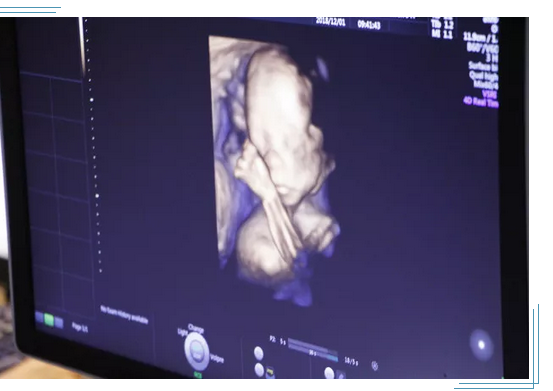

3、孕妇做四维彩超过程:四维彩超主要是检查胎儿的面部、大脑、骨骼、心脏、脊椎等有无发育缺陷,如果发现了异常可能进行的时间久比较长了,做四维彩超的整个过程大约在30分钟左右。

为了每个家庭都能拥有一个健康宝宝,大连美琳达妇儿医院斥巨资率先引进新一代·美国GE-E10四维彩超。GE-E10四维彩超能够表面成像,若胎儿有唇腭裂、四肢发育畸形、脑膜膨出、脊柱裂、腹壁裂等先天畸形,都能更清晰地查出来,也有利于医生做出判断。